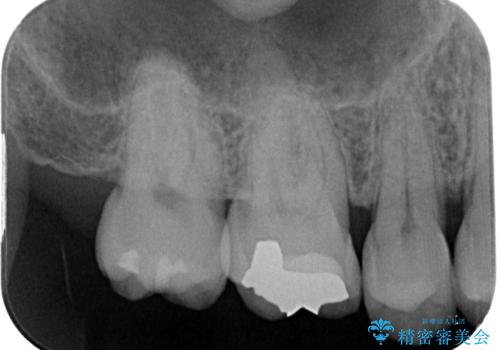

- 舌で触ると段差が気になるとのことで来院された患者様です。歯質がわずかに欠けており金属の詰め物の間に小さなギャップが生じていました。

咬み合わせも強い方なので物性、適合性に優れたゴールドインレーにて治療をしていくことになりました。

拡大鏡視野下で金属の詰め物、虫歯を除去し、ゴールドインレーに適した形に整えました。

シリコーン印象材にて型どりをしました。